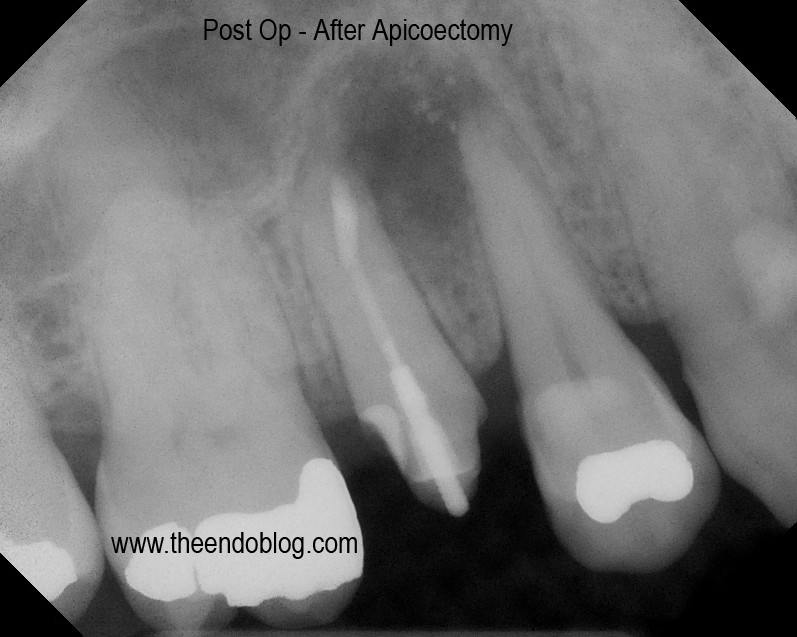

Apicoectomy completed with MTA retrofill.

9 month recall show complete healing of the periapical lesion, tooth is fully functional and asymptomatic.  This procedure saves the patient significant time and money over extraction and implant placement.